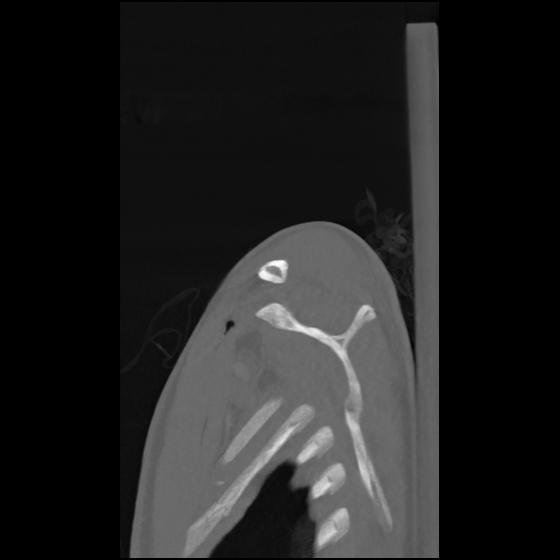

24 ANGIO,CE,Sag-MIP,5.000,ANGIO,Sag-MIP,